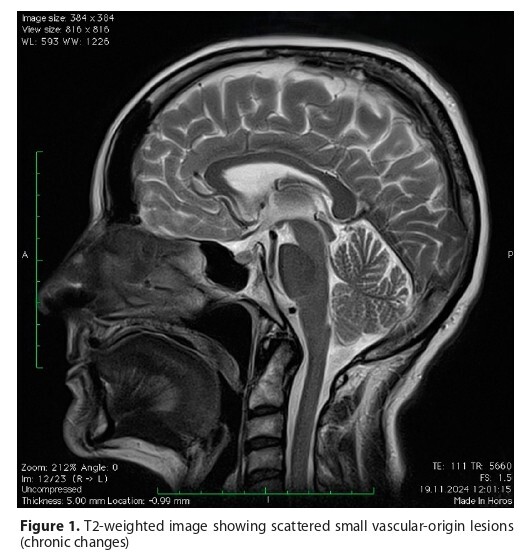

EEG revealed temporo-parieto-occipital abnormalities. Supportive treatment led to clinical improvement. The case highlights